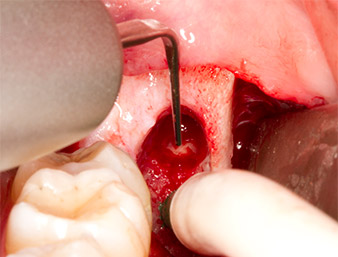

Tras una anestesia local y por conducción, el campo quirúrgico se abrió mediante los tejidos blandos para tener un acceso bucal-retromolar y se dejó expuesto (figura 3).

corte surcular

Imagen 3: El corte surcular comienza en el centro del diente 36, con alargamiento distal en la rama ascendente.

El tejido situado por encima del resto radicular no se había osificado por completo y constaba en su mayor parte de un tejido granulado con alteraciones inflamatorias (figura 4).

Imagen 4: Dos ganchos de Langenbeck y un raspador según Prichard exponen el campo quirúrgico. Se distingue un tejido granulado de la primera osteotomía que no ha cicatrizado en su totalidad.